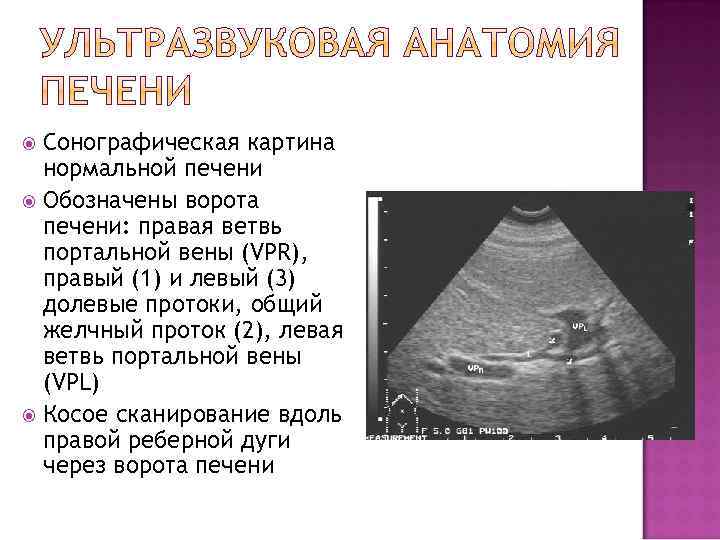

Сонографическая картина нормальной печени Структура паренхимы печени равномерная, со слабыми эхосигналами от ее внутренних структур Звукопоглощение нормальное Стенки внутрипеченочных вен практически не видны Косое сканирование вдоль правой реберной дуги через ветви внутрипеченочных вен (отмечены стрелками)

Сонографическая картина нормальной печени Визуализируются левая (1), правая (2) ветви портальной вены и косое сечение нижней полой вены (3) Стенки портальной вены гиперэхогенные, толщиной не более 2 мм Косое сканирование вдоль правой реберной дуги через ворота печени

Сонографическая картина нормальной печени Обозначены ворота печени: правая ветвь портальной вены (VPR), правый (1) и левый (3) долевые протоки, общий желчный проток (2), левая ветвь портальной вены (VPL) Косое сканирование вдоль правой реберной дуги через ворота печени